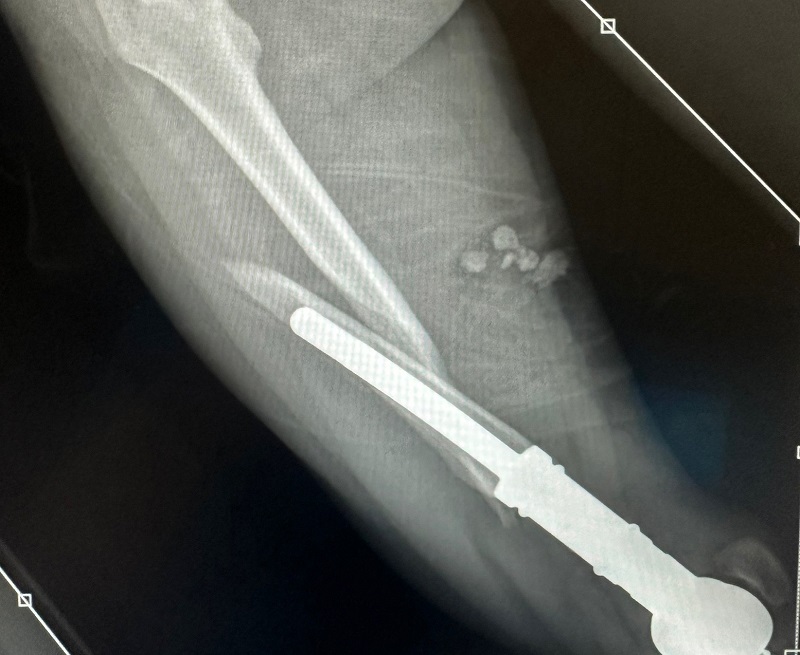

Ранее у девушки выявили опухоль, ей провели операцию по протезированию ноги.

Как сообщает Lenta.ru, девушка отправилась на Бали с подругой и во время прогулки по рисовым полям упала в яму - услышала хруст и увидела, как нога с протезом «вывернулась в другую сторону». Дарье вызвали «скорую», приезда которой она дожидалась около часа, а за перевозку в местную больницу выставили счет в 20 тысяч рублей. Несколько дней она пролежала в одной больнице, после чего ее перевезли в другую.

«Дорогие друзья! Я попала в беду. Я сейчас нахожусь на Бали и я сломала протезированную ногу. Я уже прошла через огромное количество операций и нуждаюсь в ней сейчас», - написала она. В первой больнице, где она оказалась, ей назвали неподъемную для семьи сумму.

Изначально девушка хотела попасть в Москву к своему лечащему врачу, однако в ее состояни транспортировка может быть опасной. Сейчас уроженка Сердобска ищет на Бали врача, который сможет провести лечение с учетом того, что у нее онкология.